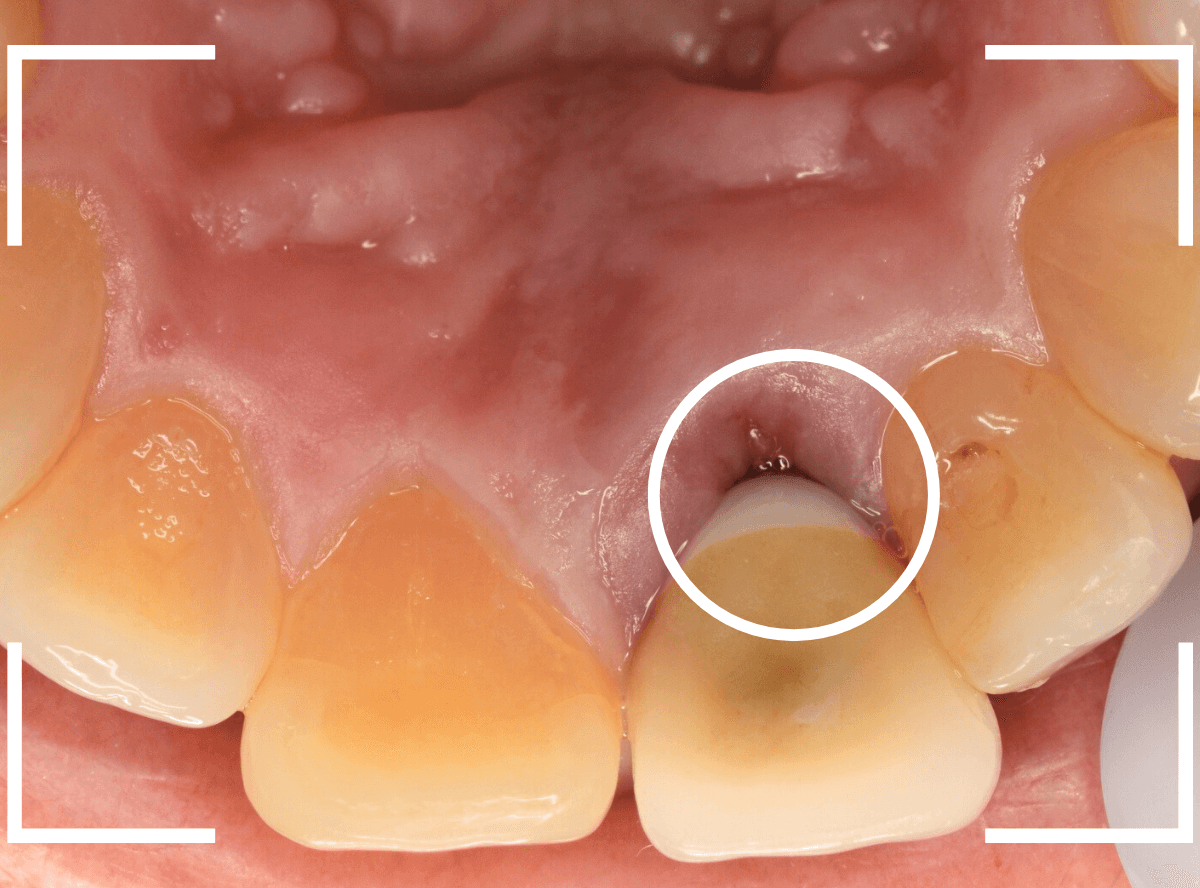

裏側を見ると少し歯肉が腫れています。

さし歯の中には大きなメタル・コアが入っています。。。

さし歯の周りの歯肉が若干黒ずんでるのも、これが原因でしょう。

せっかくさし歯をやり直すのであれば、このメタル・コアもやりなおしたいところです。

かなり怖かったですが、患者さんにも頑張っていただいて、さし歯を除去後、時間をかけて慎重にメタルコアを除去しました。

無事にメタルコアを除去できましたので、ファイバーコアに置き換えます。